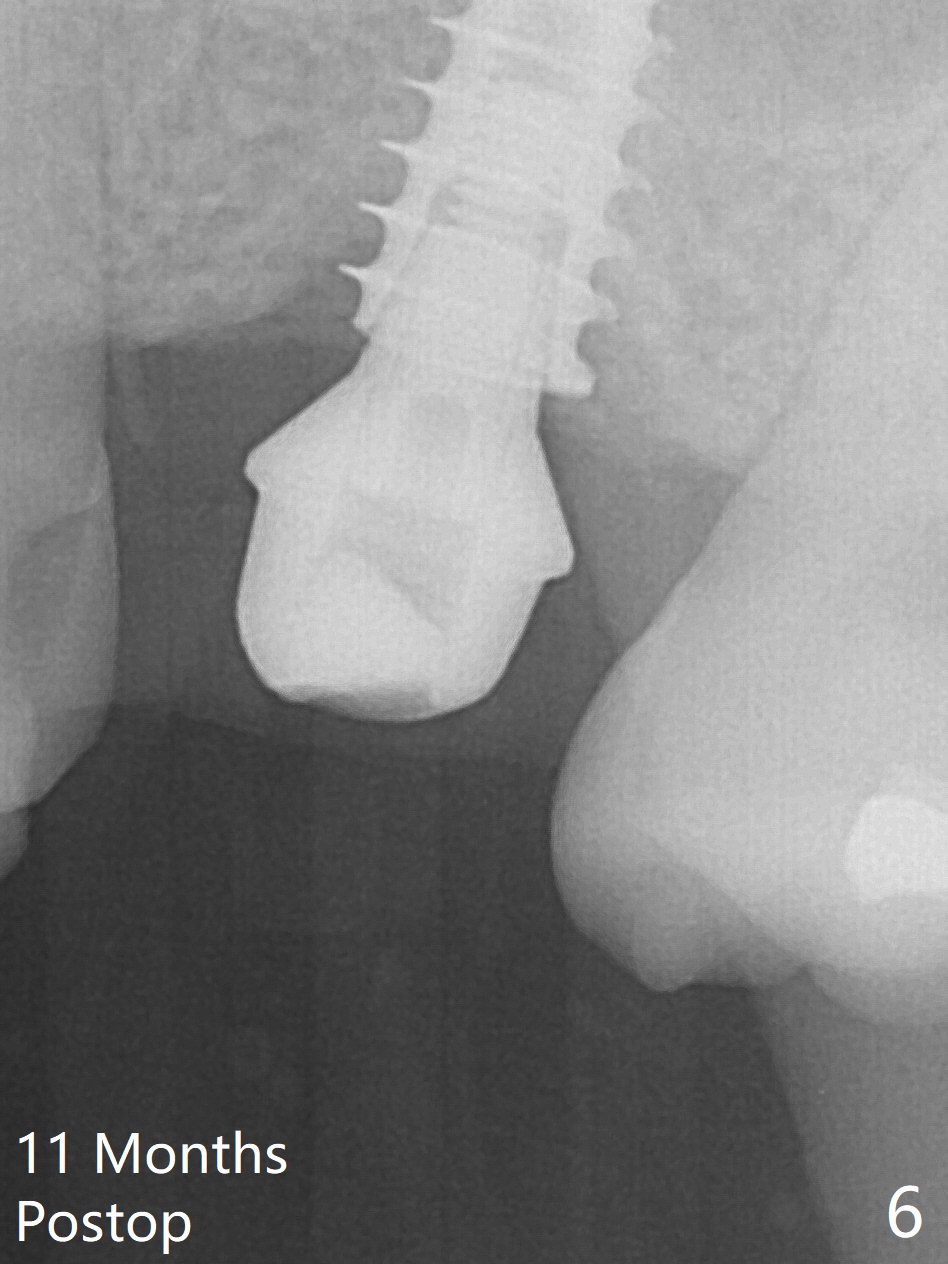

While the base of the ridge at #14 is wide, the top is moderate. IBS Magic Split is applied to gain access and test bone density (flapless). In fact the bone is hard. A 1.6 mm pilot drill is used for 9 mm (gingival level), followed by insertion of a parallel pin (Fig.1). Following Magic Expander 3.0 mm and Magic Drill 3.8 mm for ~ 11 mm (with empty feeling without air leak), a 4x11 mm dummy implant is placed with 25 Ncm (Fig.2). After insertion of a 4.5x11 mm dummy implant at 9 mm (35 Ncm; for further bone expansion), one piece of PRF plug and 1 piece of PRF membrane are pushed into the osteotomy, followed by allograft mixed with autogenous bone for sinus lift and placement of a 5x9 mm implant (Fig.3,4 with insertion torque >50 Ncm). A 6x4(2) mm abutment is placed for fabrication of an immediate provisional (Fig.5 P). There is no nasal hemorrhage postop. PRF membrane and plug are used to prevent and repair sinus membrane perforation and facilitate wound healing. There is mild bone resorption at the crest 11 months postop (Fig.6,7). The bone resorption seems to be worse 8 months post cementation (Fig.8,9); in fact the abutment screw is loose.